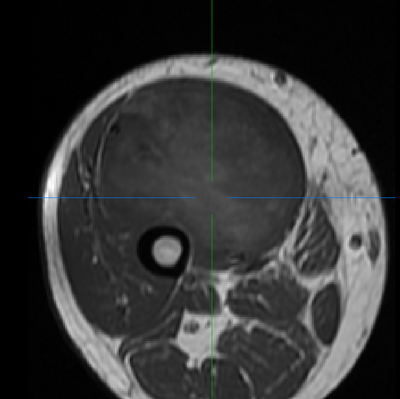

(Left/Top) T1 registered image without bias correction. (Right/Bottom) T1 image post bias correction and registration. Higher contrast and greater uniformity is apparent.